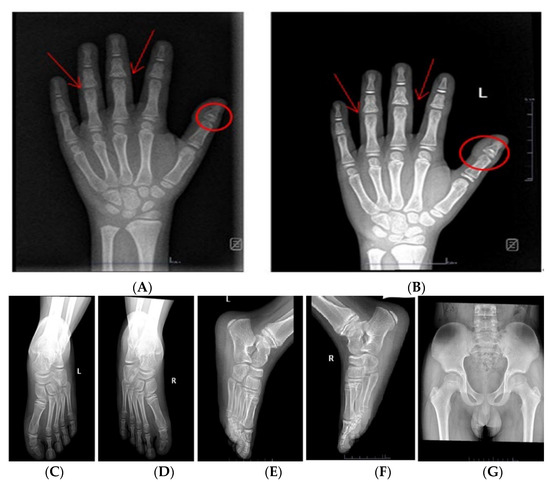

The radiograph of the left hands showed pollex phalanx epiphyses; particularly, the first proximal phalanges are characterized by cone-shaped epiphyses (circle) and are embedded with thickening of surrounding soft tissue; shortness of middle phalanges; and the middle phalanges of the third to fourth finger had a fusion of diaphysis and epiphysis. It also showed a bone age of about 9 years old according to the Greulich and Pyle method (Figure 2A). Furthermore, the anteroposterior and lateral views of the foot showed that the first, third, and fifth proximal phalanges of both feet were conical epiphyses (Figure 2C–F). The pelvis showed no obvious abnormal X-ray signs (Figure 2G). Testicular volume by ultrasound on the left was 3.54 mL and on the right was 3.24 mL. An MRI showed the normal size and location of the pituitary gland and stalk. No pathological abnormalities were found by heart, thyroid, and abdominal ultrasound.

Figure 2. X-ray report of the child: Frontal radiographic findings of the left hands of the child: (A): The photograph of the hands shows brachydactylia with shortening of the middle phalanges of all fingers. The coned epiphyses of the first proximal phalanges (circles) and more subtle, partially fused coned epiphyses of the third to fourth middle phalanges (arrows) can be noticed. Bone age (9 years) was delayed compared to chronological age (11 years). (B): The radiograph of the left hand notes a chronological age of 11 years and 6 months. (C,D): Anteroposterior radiograph of the foot; (E,F): Lateral radiograph of the foot: Foot X-ray for him demonstrates that the 1st, 3rd, and 5th proximal phalanges of both feet were conical epiphyses. (G): Plain radiographs of the anteroposterior view of the pelvis: no obvious abnormal X-ray signs in the pelvis.